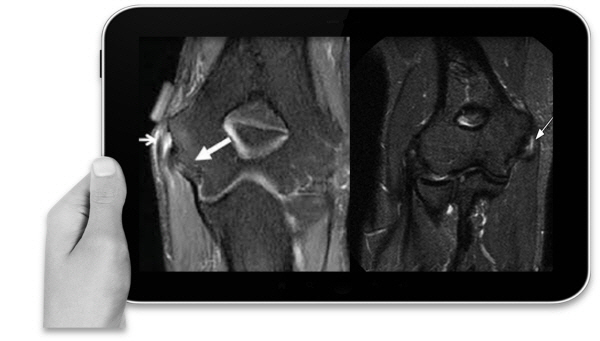

하지만 무엇보다 중요한 것은 필요한 만큼의 적정량을 필요한 부위에 시행할 수 있는지 여부라고 말했다. 테니스나 골프엘보는 내, 외측 상과부위에 염증으로 주변조직 유착 및 힘줄이 손상되는 질환이다.

따라서 손상 정도에 따라 초기-중기-말기로 구분된다. 또한 팔꿈치는 주변에 수많은 신경, 인대, 혈관 조직이 분포되어있고, 혈류공급이 원활하지 못한 저혈구간이기 때문에 성창훈 원장과 같이 주관절에 대한 해부, 생역학적 이해와 풍부한 임상경험을 갖춘 주관절 의사의 치료 여부가 핵심이라고 볼 수 있다.